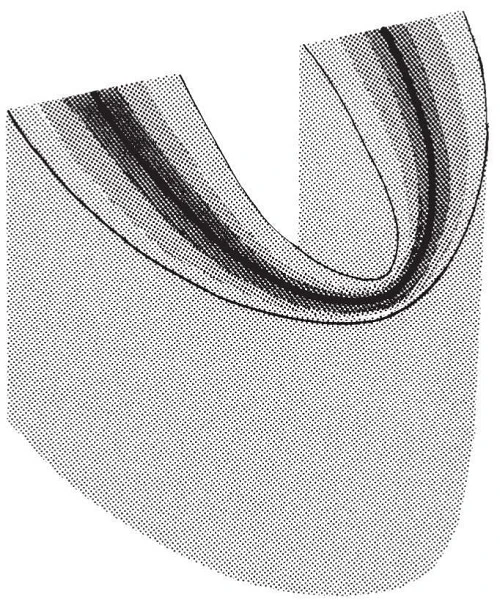

Vùng cong theo 3 chiều không gian

Lớp ảnh là một vùng cong theo ba chiều không gian, hoặc “máng tiêu điểm”, nơi những cấu trúc nằm bên trong lớp này thấy được trên phim x-quang toàn cảnh cuối cùng. Những cấu trúc được thấy trên phim toàn cảnh chủ yếu nằm bên trong lớp ảnh. Những vật thể nằm bên ngoài lớp ảnh bị mờ, bị phóng đại hoặc giảm kích thước và đôi khi biến dạng đến mức không nhận diện được. Hình dạng của lớp ảnh khác nhau tùy thuộc vào các thương hiệu thiết bị được sử dụng.

Mô tả các lớp ảnh

Hình 6 mô tả hình dạng thông thường của lớp ảnh sử dụng trong máy chụp x-quang toàn cảnh. Những nhân tố ảnh hưởng đến kích thước, độ sắc nét của hình ảnh: đường vòng cung, tốc độ thụ thể và ống chiếu tia X, và độ rộng của ống chuẩn mực. Vị trí của lớp ảnh có thể thay đổi bằng cách dùng máy mở rộng hơn, do đó có thể cần hiệu chỉnh nếu tạo ra hình ảnh dưới điểm cực thuận hằng định.